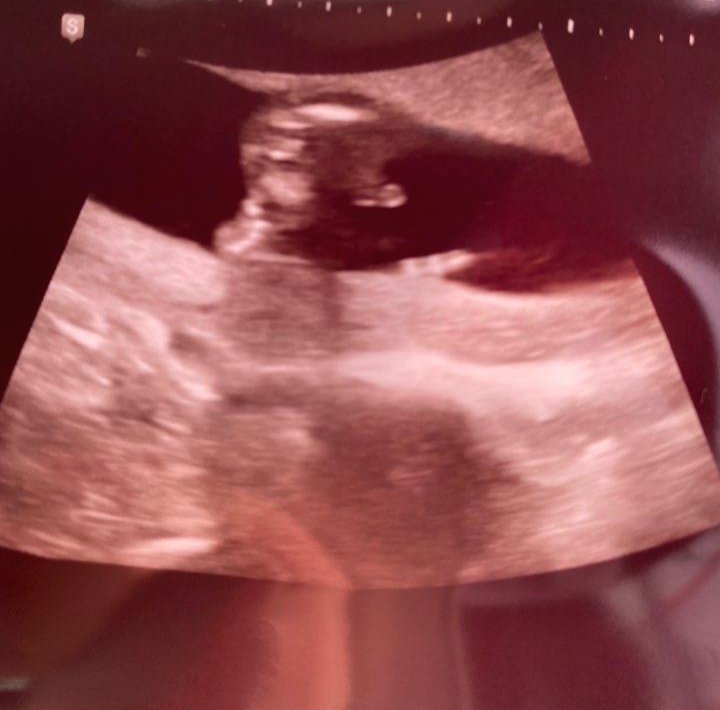

오늘은 성별을 알려준다고 하신 날이라 ㅋㅋㅋ 얼른 가고 싶더라고요. 저는 뭔가 느낌이 딱 온 게 있었지만 그래도 병원에 가서 확인을 하는 게 정확하니까 ㅋㅋ 검사를 하니 저의 예상이 적중했네요:D

그냥 전 처음부터 아들일 거 같았거든요. 역시나 아들이라고 자기를 드러내더라고요ㅋㅋ 의사 선생님이 95%라며 ㅋㅋㅋ 튀어나온 게 크기도 크다고 웃으시면 말하더라고요ㅋㅋㅋㅋ 어찌나 웃기던지 ㅋㅋㅋㅋ

저희 아들 초음파 사진 보여드릴게요:D